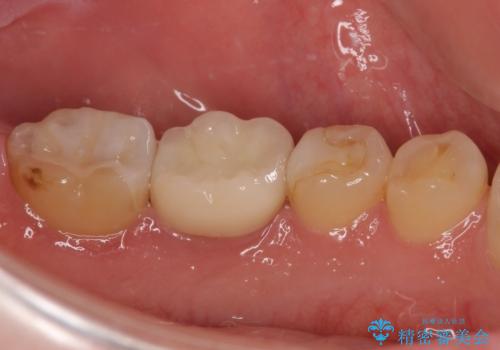

奥歯は虫歯が放置されていましたが、特に症状はなく歯髄の状態も正常でした。

前歯、奥歯ともにオールセラミッククラウンやセラミックインレーにて治療を行うこととしました。